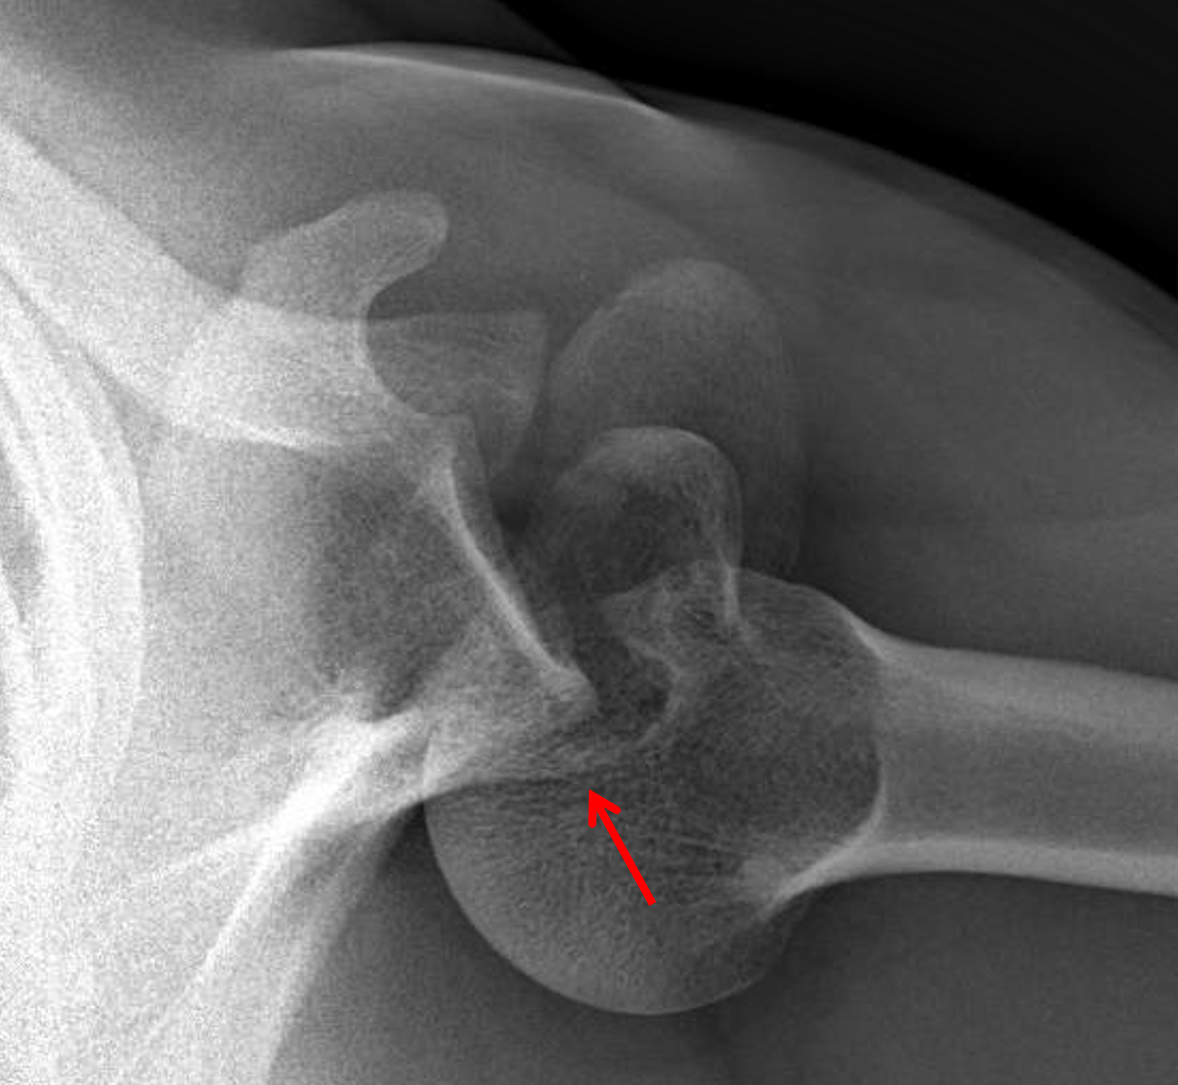

Periprosthetic fracture of the glenoid: The posterior labrum is avulsed, and stripped scapular periosteum remains attached to the posterior labrum (arrowhead).

An impaction fracture is also present at the posterior glenoid rim (blue arrow). Posterior glenoid fractures although rare can lead to recurrent instability. Operative techniques often involve a large dissection to view the fragments resulting in local soft. #posterior glenoid fracturearthroscopic fixationwe performed the surgery in lateral position with arthroscopic reduction and fixation with 2 c c screws.this. Arthroscopic posterior glenoid fracture fixation using knotless suture anchors. Posterior dislocations are uncommon and easily missed, because there is less displacement compared to the anterior dislocation. Shoulder instability after a posterior glenoid rim fracture is rare and potentially difficult pathology to treat. Or incomplete neck fracture top. Etiology, natural history, anatomy, clinical evaluation, xray / diagnostic tests glenoid fracture clinical evaluation. Arthroscopic fixation of posterior glenoid fracture подробнее. Shoulder instability after a posterior glenoid rim fracture is rare and potentially difficult pathology to we describe an arthroscopic technique for posterior glenoid rim fracture fixation using knotless. Classification of glenoid cavity fractures: • fracture of the base of the coracoid process and glenoid neck fracture • glenoid cavity fracture and disruption of the superior shoulder suspensory complex slight retraction and posterior rotation of the arthroscope will allow examination of the posterior. Glenoid fracture exits at lateral. (obq08.134) the modified judet approach to the posterior scapula exploits the internervous interval between what two muscles? Impaction fracture of anteromedial humeral head. Isolate fracture of lesser tuberosity.